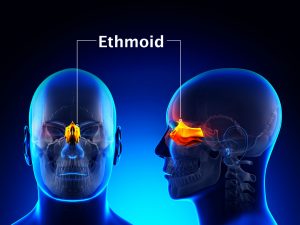

Whereas acute stress resulting from trauma may temporarily block pain, chronic physical or emotional stress can cause pain and lowering your tolerance to pain, stress makes existing discomfort worse. For example, if you are worried that pain results from a serious disease, it may be hard to bear, but once you know that this is not the case, you may find the pain much more tolerable. Long-term stress also causes physical tension, which makes you prone to headaches and minor injuries, such as strained muscles.